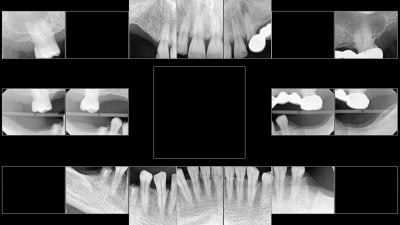

Why I Invested Digital Imaging Reliable Imaging for Comprehensive Dentistry By Paresh Shah, DMD July 01, 2024 7 min read